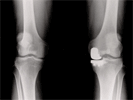

Follow

Up

Patient had normally aligned knees with good relief of knee pains

Progress

Good relief of knee pain and full return of knee motion